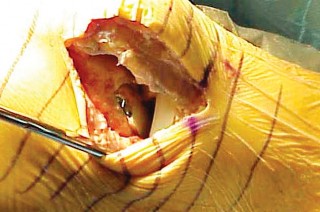

الشق الجراحي:

يُستخدم شق طولي في الجانب الإنسي (الداخلي) من الركبة. يجب أن يكون الشق كبيرًا بما يكفي لتوفير رؤية جيدة للمفصل الرضفي الفخذي وإمكانية التحويل إلى TKA.

- فتح المفصل (Arthrotomy): يكون الفتح خطيًا وموازياً لألياف الوتر الرضفي، ويمتد إلى عظم الظنبوب وإلى الجزء السفلي من الرضفة.

- تحرير الأنسجة الرخوة: يتم قطع الغضروف الهلالي لتحرير الأنسجة الرخوة من عظم الظنبوب، ويتم تطوير سديلة تحت السمحاق في نمط دائري حول الظنبوب. يُمدد هذا التحرير خلفيًا لضمان توازن الأربطة.

-

تصحيح التشوه:

الهدف هو تحقيق تصحيح طفيف للتشوه، مع وجود رخاوة كاذبة طفيفة عند تطبيق ضغط تفحجي في نهاية الإجراء. يجب تجنب التصحيح المفرط.